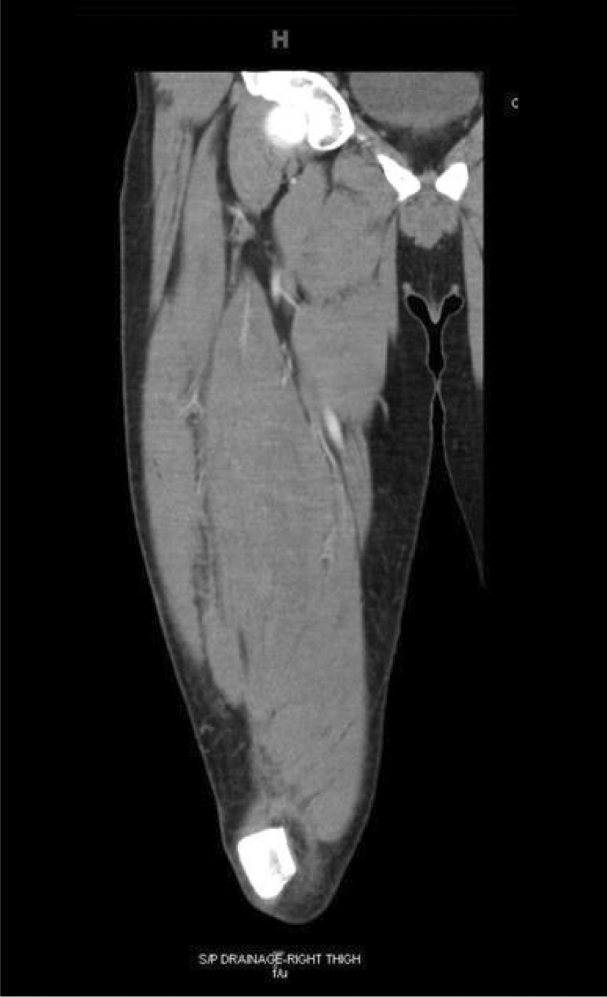

Four days later upon evaluation in the surgical clinic for follow up, he was found to be febrile with a tense right thigh and mild to moderate edema. Local wound exploration done at the clinic was unsuccessful to fully delineate the extent of the fluid collection and concern for residual abscess prompted referral to the emergency department for further evaluation. In the ED the patient underwent multichannel axial imaging of the right lower extremity with intravenous contrast. Comparison with prior lower extremity CT angiogram showed evidence of large residual abscess associated with the right quadriceps with minimal interval change (Fig. 2). An elongated 1.3 cm hyperdensity was again demonstrated in the dependent aspect of the fluid collection, likely representing a foreign body. Soft tissue swelling was noted at this level with post drainage changes and a small amount of air in the soft tissues. The quadriceps muscle appeared expanded slightly more than on the previous study.

Figure 2.

Coronal CT of the right thigh depicting large residual abscess associated with the right quadriceps with minimal interval change.